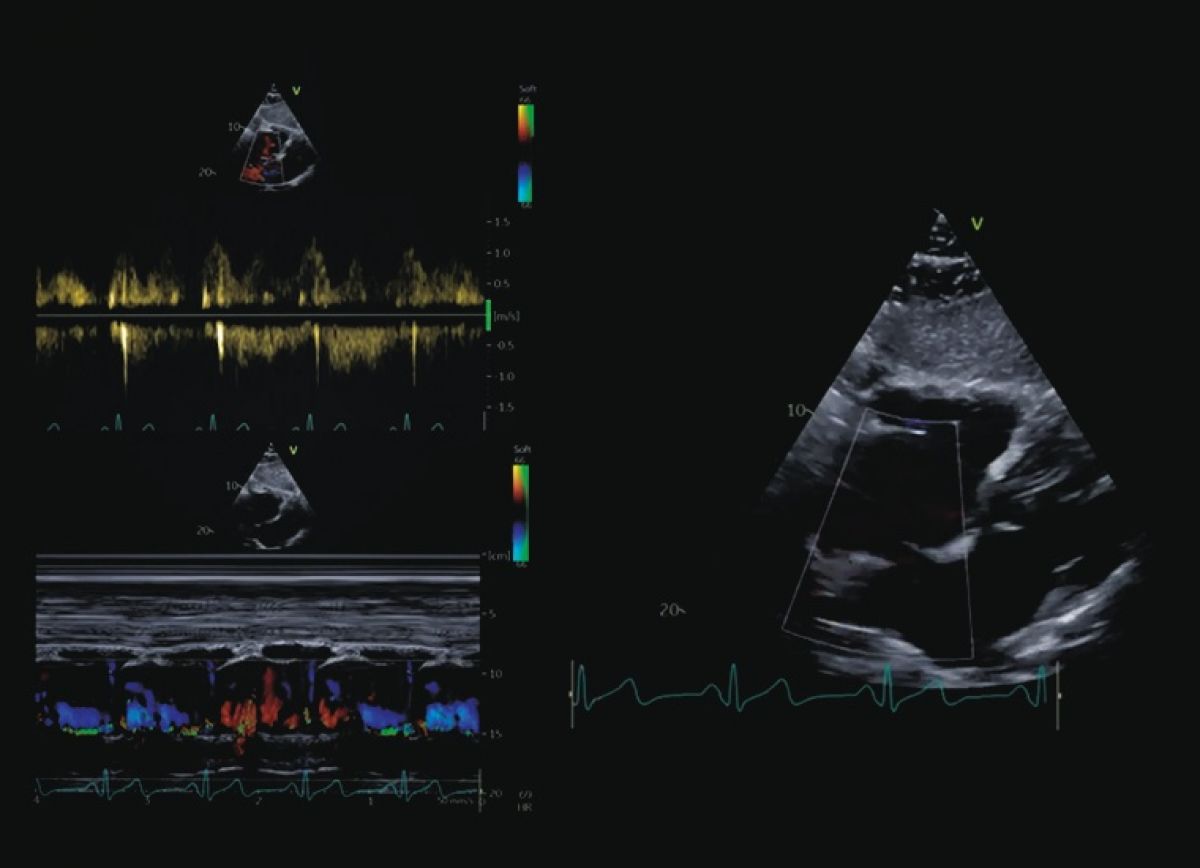

Pacjent z trzepotaniem przedsionków; w wywiadzie niewielkie pogorszenie tolerancji wysiłku i napadowe kołatania serca od około roku

Ubytek w przegrodzie międzyprzedsionkowej typu otworu wtórnego

Echokardiografia przezklatkowa i przezprzełykowa

Ocena ubytku w przegrodzie międzyprzedsionkowej

Ocena prawych jam serca

Kwalifikacja do przezskórnego zamknięcia ubytku w przegrodzie międzyprzedsionkowej